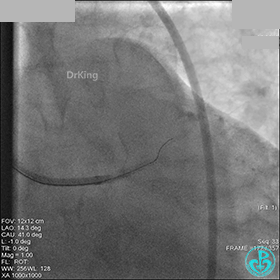

右冠脉血流3级,患者无症状,终止手术。

术后患者无特殊不适。

1周后再次上台,右冠脉3级血流,3段局限性严重狭窄,内膜模糊,应该是上次操作夹层遗留下的血肿。